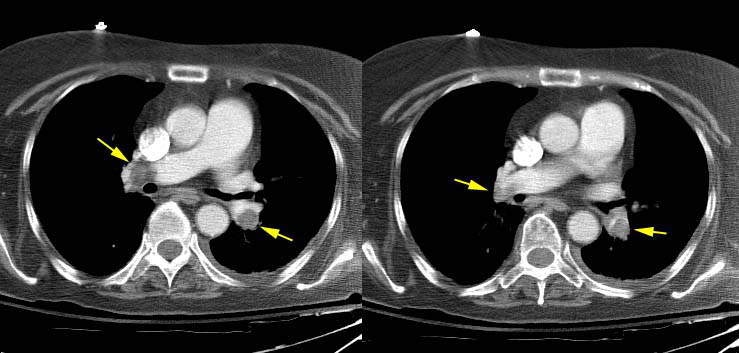

Vascular > Dissection > Images > TypeA > Case2